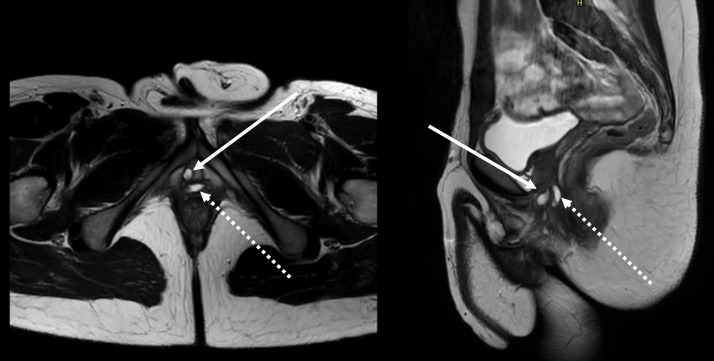

Urethral diverticulae at the level of the perineal urethra may be asymptomatic if small, or if larger may lead to increase in post-void dribbling, pelvic pain, or recurrent infections (24). These should be distinguished from a persistent vaginal cavity or regrowth of the vaginal canal, which may present as prolonged and high-volume post-void dribbling, pelvic or perineal pain or fullness, “perineal cysts,” and urinary tract infections (5,62). These remnants may communicate with the urethra, forming essentially a urethral diverticulum through the associated urethrovaginal fistula, or may not communicate with the urethra and be a mucocele. Urologic evaluation should include assessment for urethral stricture, as distal obstruction may transmit pressure through the suture lines and into the previously obliterated vaginal canal (50). MRI is often helpful at diagnosing remnants and demonstrating their size and relationship to surrounding anatomy (63) (Figures 5,6). Flexible cystoscopy is a useful adjunct in identifying strictures and/or communication between the urethra and the remnant. Incomplete vaginectomy or inadequate de-epithelialization predispose to this condition. Excision and attempt at obliteration of the vaginal remnant can be done through open perineal or transabdominal/robotic-assisted approaches (34) (Figure 7).

Figure 5.

MRI demonstrating Skene’s gland cyst (white solid arrow) and vaginal remnant (white dotted arrow) in a patient who underwent metoidioplasty with subsequent secondary phalloplasty and vaginectomy.